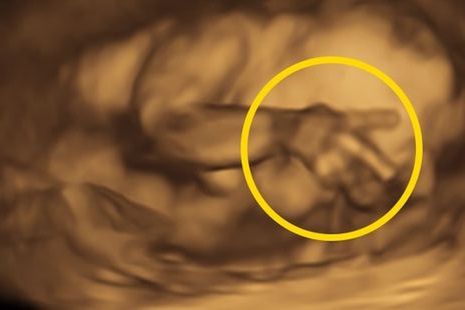

Następnie dziewczynka pokazała też "znak pokoju", co wszyscy odebrali jako przeprosiny za pierwszą reakcję.